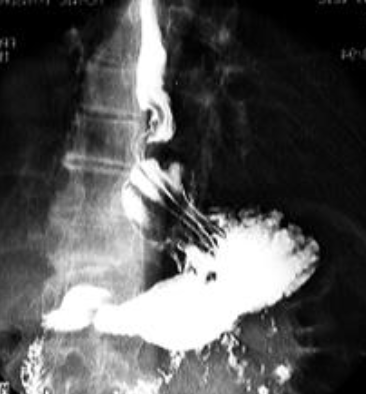

Neoplasm malign gastric vegetant

Neoplasm malign gastric ulcerant

Neoplasm malign gastric ulcero-vegetant